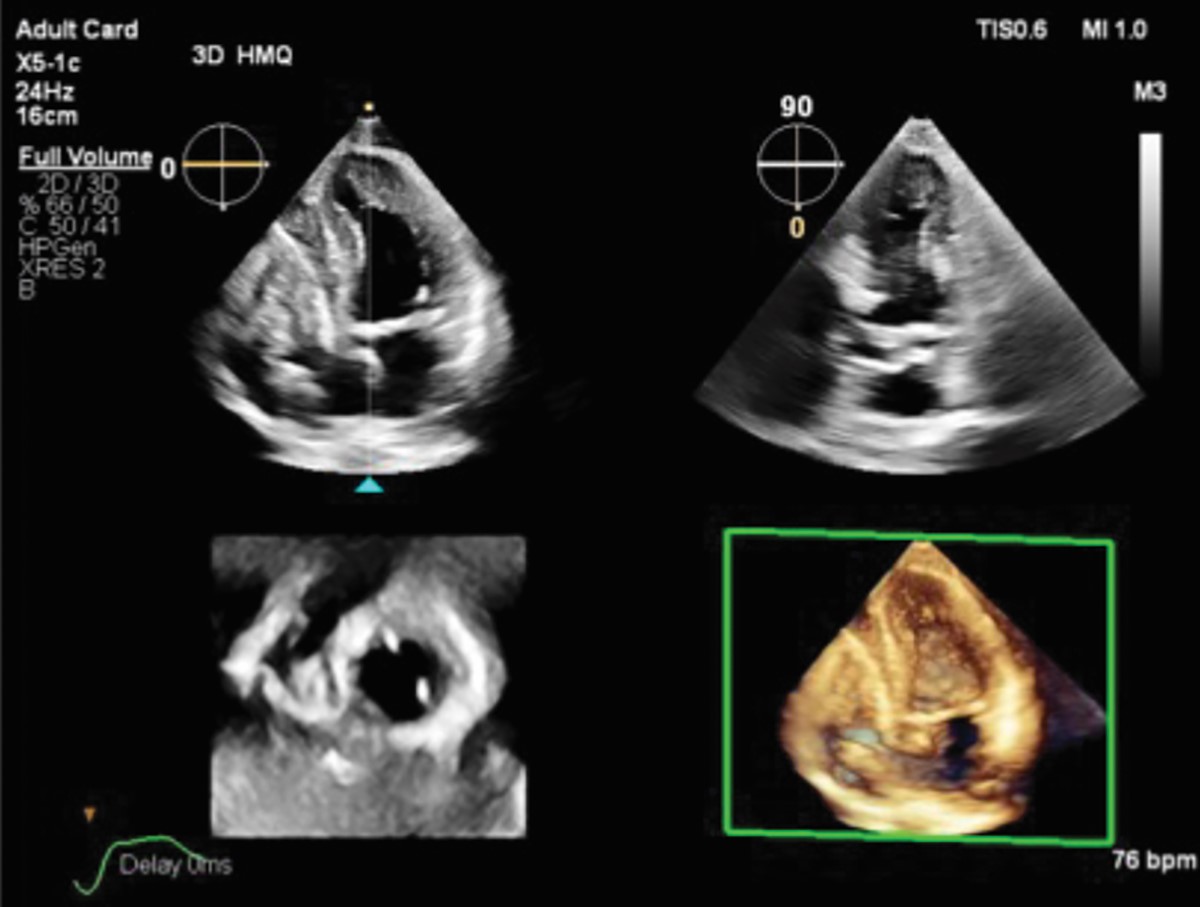

Transcend Plus visibly improves sharpness, contrast, and detail in 2D and 3D imaging, featuring the latest FDA-cleared enhancements for EPIQ CVx and Affiniti CVx. These upgrades support superior visualization of cardiac anatomy and function, enabling diagnostic confidence even in the most complex or technically challenging cases. The update also introduces the new 2D Auto EF Advanced feature, expanding AI capabilities for contrast images – essential for accurately assessing cardiac function.

Left ventricular (LV) function assessment is one of the most critical applications in cardiac imaging, playing a central role in diagnosing and managing a wide range of cardiac conditions. Transcend Plus directly supports this need by delivering fast, reproducible results that help cardiologists quickly and definitively evaluate LV function consistently across different patients and over time. Automated tools minimize operator variability, ensuring more reliable and standardized measurements, especially vital in high-volume or high-pressure clinical environments. In addition, Transcend Plus offers robust support for both contrast and non-contrast imaging. The 2D Auto EF feature enables accurate assessments even when contrast agents cannot be used, such as in patients with renal impairment. Building on this, 2D Auto EF Advanced adds AI-powered quantification capabilities for both contrast and non-contrast studies, broadening clinical applicability and enhancing measurement reliability in patients with poor image quality or challenging acoustic windows. These capabilities combine to deliver a more confident, efficient approach to cardiac care.